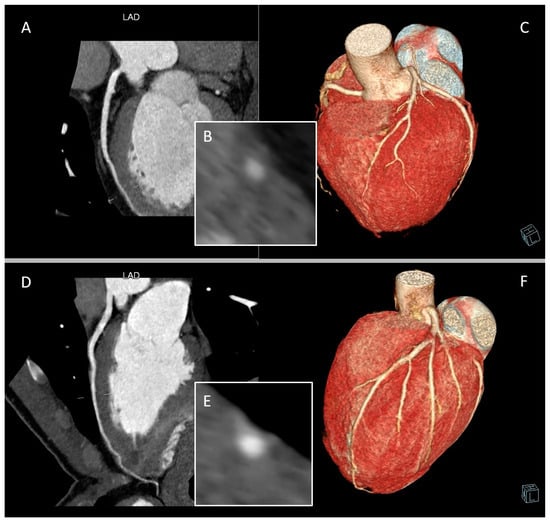

2. CCTA Imaging Protocol

3. Role of CCTA: Anatomical Evaluation